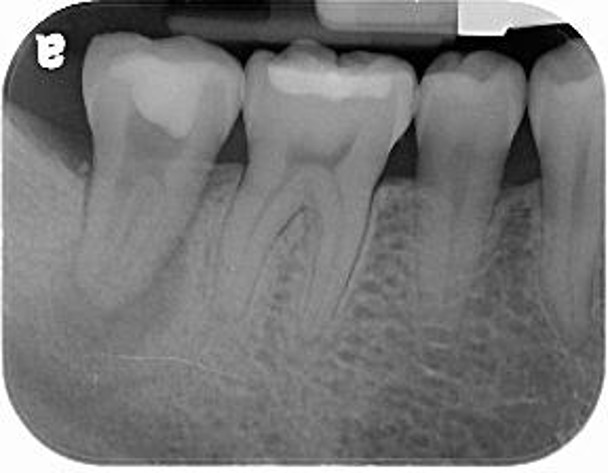

治療前,根管後大臼齒有牙裂

治療前,根管後第一大臼齒有牙裂

拔牙後進行骨脊保存術